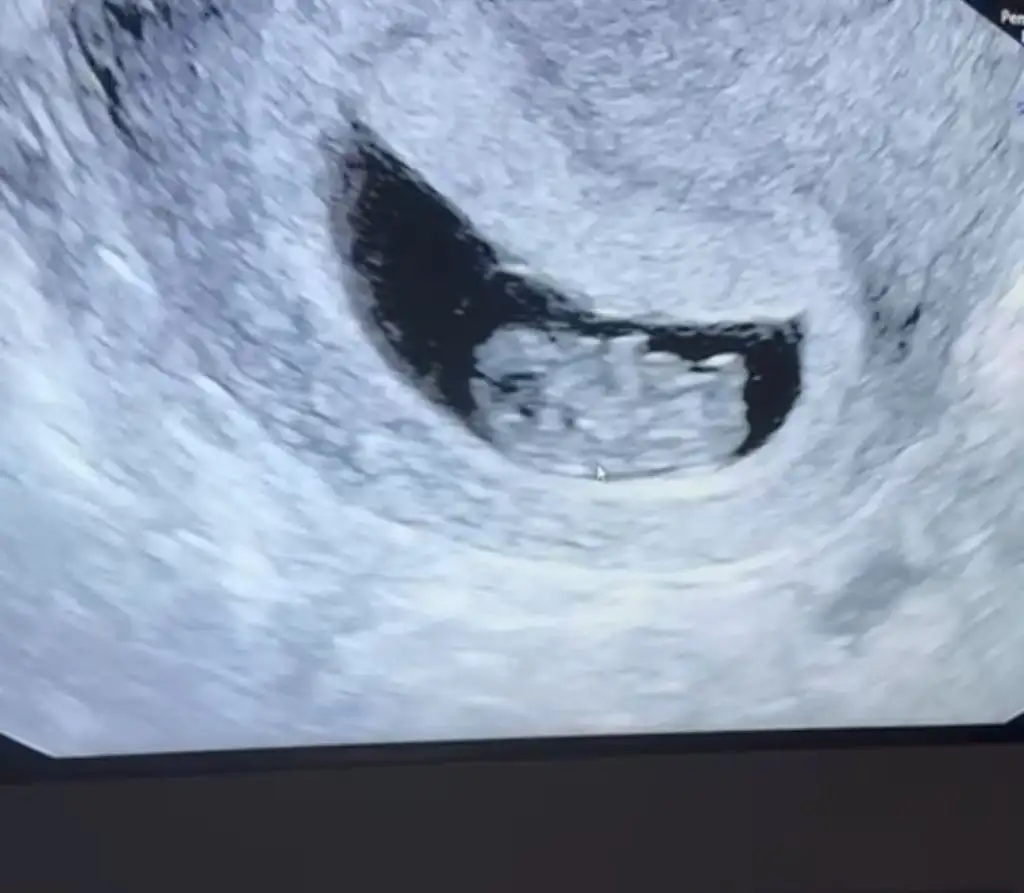

ben de araya kaynasam? daha önce buraya atmıştım ama hiç tahminde bulunan olmadı.ilki 6 hafta ikincisi 7+3.6-7 haftalık ultrason varmı yollar mısın Bi daha bakim merak ettim

doktor bir şey demedi ama.Vajinal ultrason ise erkek karın ultrasonu ise kızben de araya kaynasam? daha önce buraya atmıştım ama hiç tahminde bulunan olmadı.ilki 6 hafta ikincisi 7+3.

cuma günü ikili tarama için gittiğimde görüğüm şey kordon değilse erkek gibiydidoktor bir şey demedi ama.

Kız bence

Kıza benziyor

Bana da yorum yapar mısınKıza benziyor